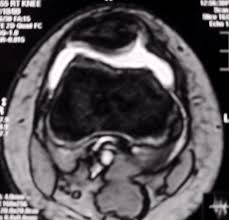

Patients usually present with insidious onset anterior knee pain aggravated by physical activity. MRI shows femoropatellar incongruence with lateral positioning of the patella suggesting lateralizationThis is refered to as excessive lateral pressure syndrome better demonstrated in various femoropatellar articulation X-rays. This may put strain on the medial side and tenderness in the region of the medial patellofemoral ligament MPFL.

Excessive Lateral Pressure Syndrome Mri Sumer S Radiology Blog